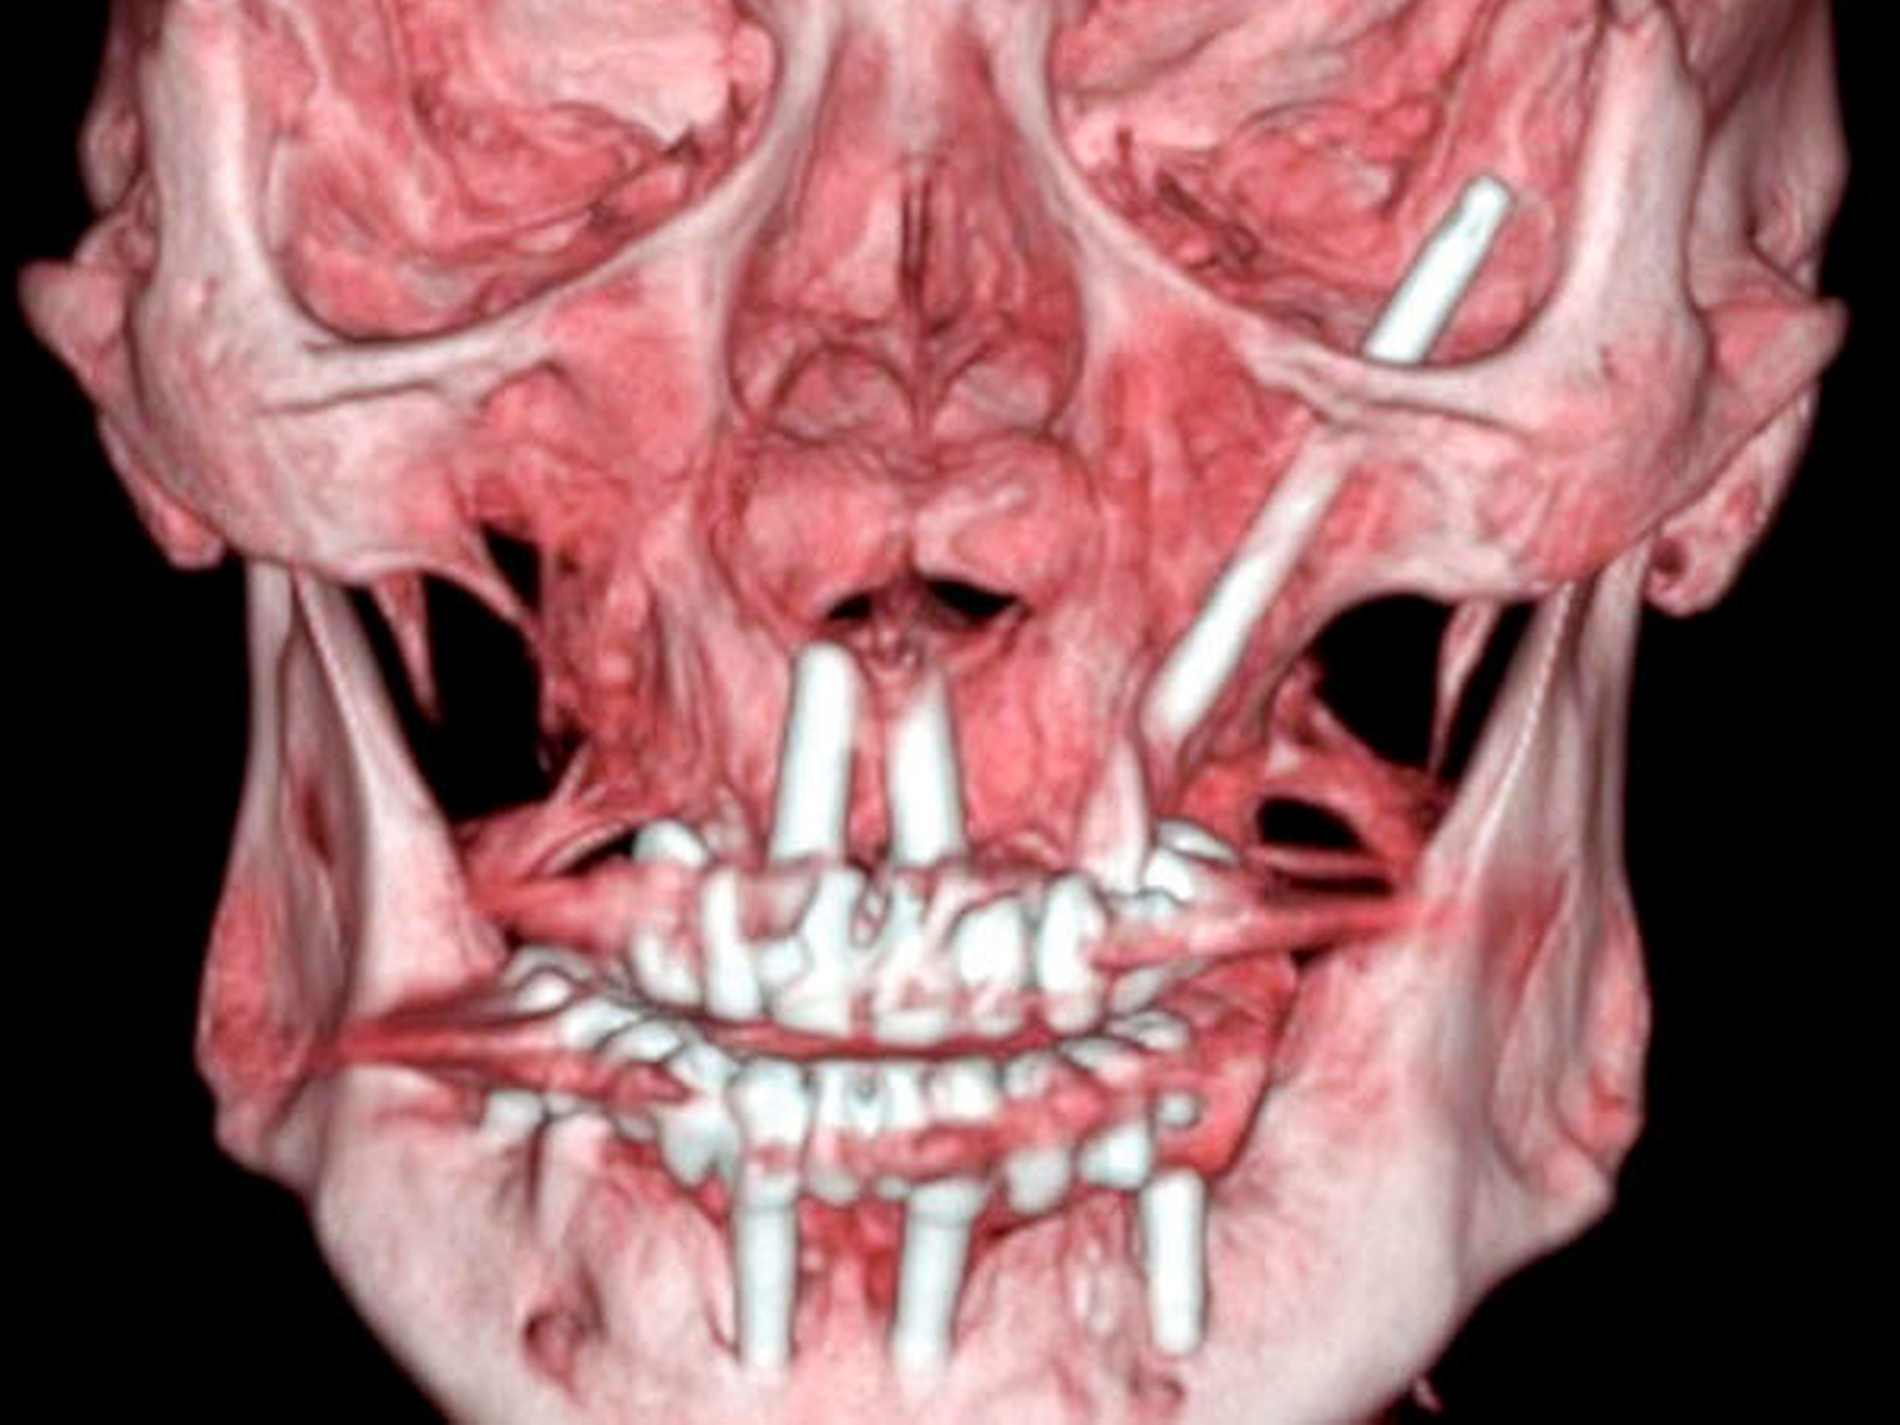

Zur weiteren Abklärung erfolgte nach zweidimensionaler Beurteilung die dreidimensionale Rekonstruktion der CT-Daten. Hierbei kamen die röntgenopaken Implantate im Kiefer sehr gut zur Darstellung und konnten in Bezug auf deren anatomische Lage beurteilt werden. Im atrophen Ober- und Unterkiefer zeigte sich ein mittelgradiger horizontaler Knochenabbau mit vertikalen Einbrüchen an allen Implantaten. In der rechten Maxilla regio 016 bestand nach Explantation eines rechtsseitigen Zygoma-Implantats ein circa 2 cm großer Defekt, der, aufgrund der verdrängten Weichgewebe und Lufteinschlüsse sicher bis in die mittlere, zentrale Orbita reichte.

Als auffälliger Nebenbefund fand sich auch auf der linken Seite ein 60-mm-Zygoma-Implantat, das 17 mm in die linke Augenhöhle ragte. Neu aufgetretene Veränderungen oder Behinderungen in diesem Bereich waren vom Patienten subjektiv nicht wahrgenommen worden, die Implantation selbst lag bereits zehn Jahre zurück.

Das Problem beim Einbringen der Zygoma-Implantate ist die korrekte Positionierung in den Jochbeinkörper. Hier kann es besonders beim liegenden Patienten leicht zu einer Via falsa kommen. Im vorliegenden Fall wurden die 60 mm langen Zygoma-Implantate statt in den Jochbeinkörper beidseits in die Orbita gesetzt. Das Problem der möglichen Fehlpositionierung langer Fixturen und von Zygoma-Implantaten wurde früh erkannt und es wurden hierfür Navigationshilfen entwickelt [Stella et al., 2000]. Schiroli et al. beschrieben 2011 eine Methode zur Computer-navigierten Insertion dieser Implantate. Sie wiesen auf der Basis ihrer Erfahrungen mit 25 Implantaten darauf hin, dass Komplikationen auch mit der Navigation nicht vollständig ausgeschlossen werden können [Schiroli et al., 2011].